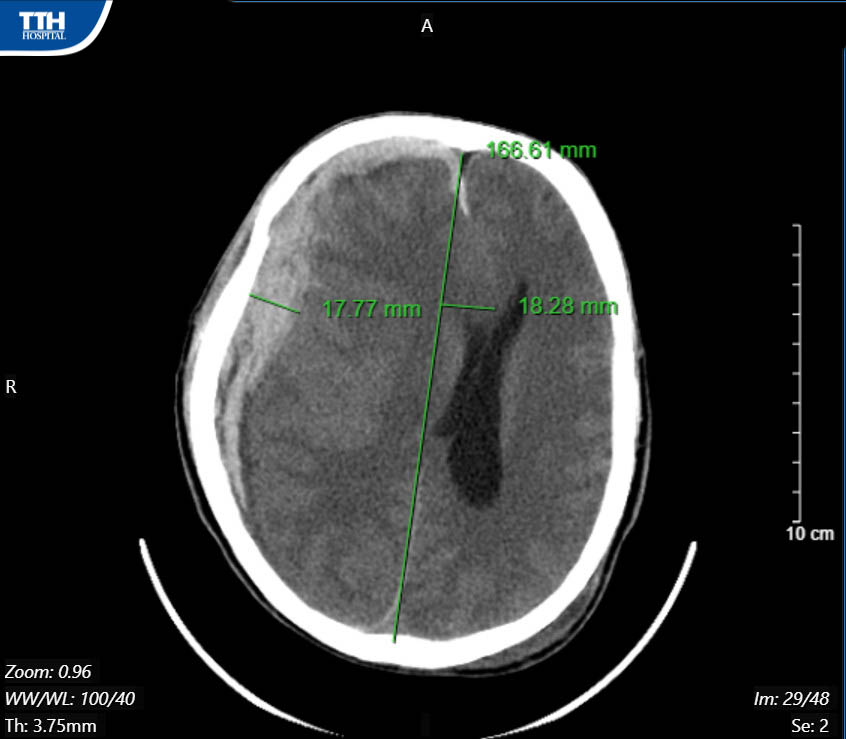

Bệnh nhân V vào viện trong tình trạng hôn mê, glasgow 6 điểm, liệt nửa người trái. Kết quả chụp cắt lớp vi tính phát hiện tụ máu dưới màng cứng bán cầu phải cấp tính độ dày 18 mm gây đè đẩy đường giữa 18 mm.